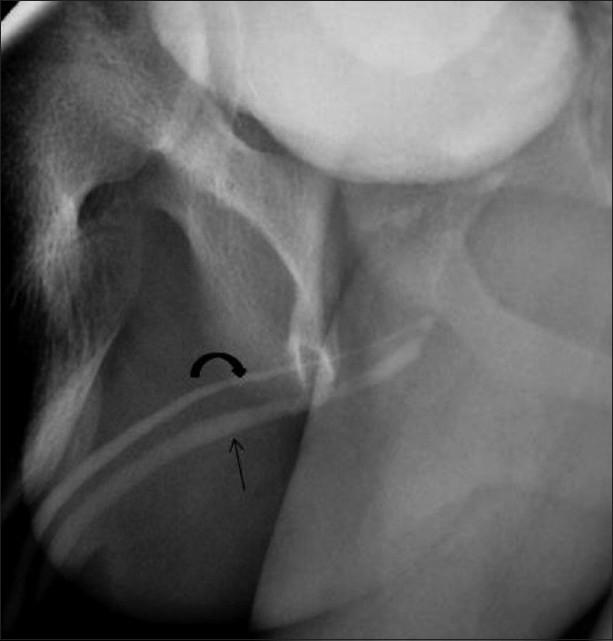

Congenital anomalies of the male urogenital tract are common. Some lesions like posterior urethral valve or anterior urethral diverticulum tend to present early in infancy and are often easily diagnosed on conventional contrast voiding cystourethrograms. Other conditions like posterior urethral diverticulum or utricle can be relatively asymptomatic and therefore present late in childhood. We present the spectrum of imaging findings of common and uncommon anomalies involving the male urethra. Since the pediatric radiologist is often the first to make the diagnosis, he or she should be well aware of these conditions.

男性泌尿生殖道先天性异常很常见。一些病变,如后尿道瓣膜或前尿道憩室,往往在婴儿期早期出现,通常在传统的排尿性膀胱尿道造影上很容易诊断。其他情况,如后尿道憩室或前列腺囊,可能相对无症状,因此在儿童期晚期出现。我们展示了涉及男性尿道的常见和罕见异常的影像学表现谱。由于儿科放射科医生往往是第一个做出诊断的人,他或她应该充分了解这些情况。